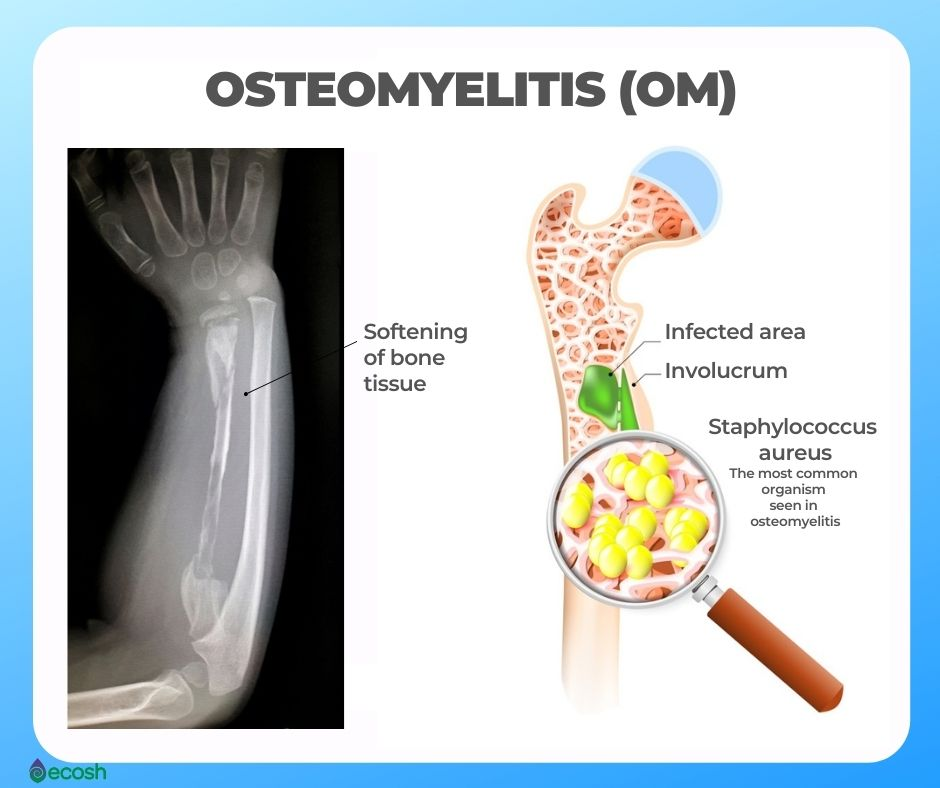

- explain osteomyelitis (ઓસ્ટીઓ માયલાઇટીસ ને વર્ણવો).

ઓસ્ટીઓ માયલાઇટીકસ એ બોનનું તથા સરાઉન્ડીંગ ટીશ્યુસ નું પાયોજનિક ઇન્ફેક્શન છે.

ઓસ્ટીઓમાયલાઇટિંસ મા બોન નુ ઇન્ફેક્શન થાય છે અને તેમાં મુખ્યત્વે કોર્ટેકસ તથા મેડ્યુલારી પોસૅન નું ઇનવોલ્વમેન્ટ થાય છે.

ઓસ્ટીઓમાયલાઇટિંસ એ બોન નુ એક્યુટા ઇન્ફેક્શન છે. તે મુખ્યત્વે એક્યુટ, સબએક્યુટ તથા ક્રોનીક પ્રોસેસમાં હોય છે.

explain Etiology/cause of Osteomyelitis (ઓસ્ટીઓમાયલાઇટિંસ ના કારણ જણાવો)

- સ્ટેફાઇલોકોકસ એયુરિસ ,

- ઇ કોલાઇ,

- સ્યુડોમોનાસ,

- પ્રોટીયર્સ,

- સાલ્મોનેલા,

- રૂયુમેટોઇડ આર્થરાઇટિસ,

- સિકલ સેલ ડીઝીઝ.

explain Diagnostic evaluation of the Osteomyelitis (ઓસ્ટીઓ માયલાઇટીસ ના ડાયગ્નોસ્ટિક ઇવાલ્યુએશન લખો).

- history tacking and physical examination,

- બોન X Ray,

- ct scan,

- MRI,

- બ્લડ ટેસ્ટ,

- બ્લડ કલ્ચર,

- નીડલ એસ્પિરેશન,

- બાયોપ્સી,

- બોન સ્કેન,

- બોન બાયોપ્સી,

- બોન X Ray,

- કમ્પલીટ બ્લડ કાઉન્ટ,

- C રિએક્ટીવ પ્રોટીન,

- એરિથ્રો સાઇટ સેડીમેન્ટેશન રેટ( ESR ),

- MRI ઓફ બોન ,

- નીડલ એસ્પિરેશન,